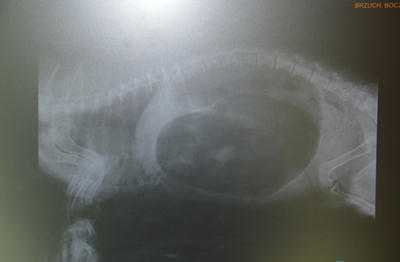

Skręt żołądka.